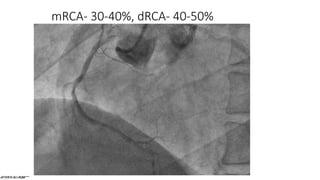

mRCA- 30-40%, dRCA- 40-50%